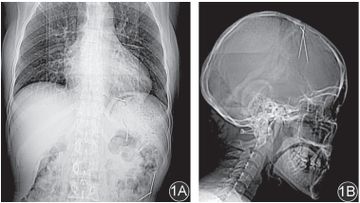

Dokter menemukan jarum besi misterius di rongga dada, perut, dan kepala seorang pasien wanita. Tak pernah diketahui, jarum besi tersebut berasal.